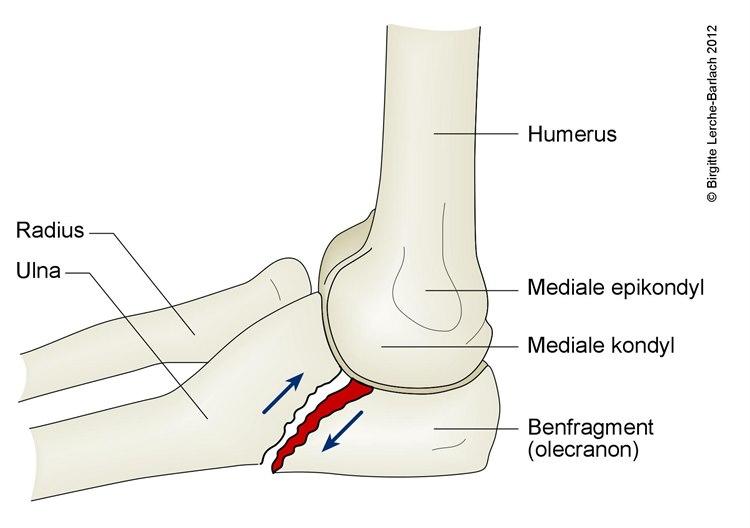

Skader mot bein, ledd og muskler innbefatter beinbrudd, ledd ut av stilling (dislokasjoner), overstrekninger og overrivninger. Et bein kan være brekt tvers over, på langs (ofte spiralformet) eller beinet er knust/sprukket. Et ledd kommer ut av stilling når et av dets bein blir skjøvet ut av sin normale posisjon. En overrivning skjer når leddbånd som holder beinene sammen i leddet eller muskelsener, blir overrevet. En overstrekning er en overstrukket muskel eller sene (den delen som fester muskelen til beinet).

Bruddet kan være stabilt, der bruddendene står riktig mot hverandre, eller ustabilt, der bruddendene ikke står mot hverandre og kan beveges i forhold til hverandre. Ustabile brudd kan føre til at beinpipene stikker ut gjennom huden. Hvis en bruddende stikker gjennom huden, sier vi at bruddet er åpent. Hvis huden er inntakt, er bruddet lukket. Et åpent brudd innebærer en betydelig infeksjonsrisiko.